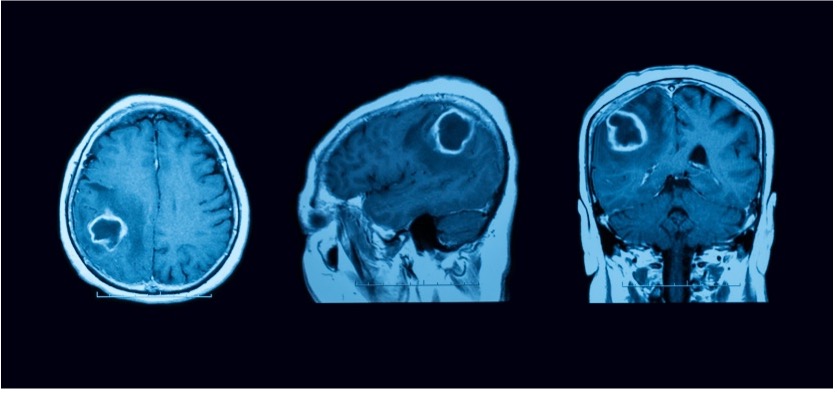

טיפול באמבוליזציה של גידולי מוח

ישנם גידולי מוח עם אספקת דם עשירה המודגמת גם ב- MRI. טרם כריתה כירורגית, ניתן "לחנוק" את הגידול באמצעות חסימה יזומה של האספקה העורקית של הגידול. זו מתבצעת בעזרת הזרקת חומר תסחיפי נוזלי (על בסיס אלכוהול) בעורקים המזינים את הגידול, טרם הניתוח הפתוח לכריתתו. כך ניתן "לייבש" את הגידול מאספקת דם עורקית, לעודד נמק עוד בטרם כריתתו ולהקטין משמעותית את שיעור הדימום בעת הניתוח הסופי – ובכך לקצר את משך הניתוח ומשך ההרדמה, שכן המנתח מתמודד פחות עם דימומים פעילים בעת הניתוח. כתוצאה מכך המנותח יזדקק פחות למנות דם.

אמבוליזציה משביתה את אספקת הדם לגידול ומפחיתה את איבוד הדם במהלך כריתה כירורגית.